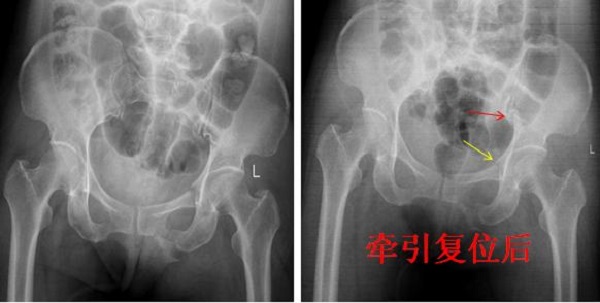

骨盆骨折是創(chuàng)傷骨科最為嚴(yán)重骨折類型之一,傳統(tǒng)骨盆骨折手術(shù)行切開復(fù)位內(nèi)固定術(shù),手術(shù)時(shí)間長(zhǎng),創(chuàng)傷大,圍手術(shù)期出血多,術(shù)后患者恢復(fù)慢并發(fā)癥較多。近年來,骨盆骨折微創(chuàng)化治療成為一種趨勢(shì),通過閉合復(fù)位或有限切開...